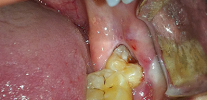

La foto sotto mostra la radice del dente rotto da rimuovere: